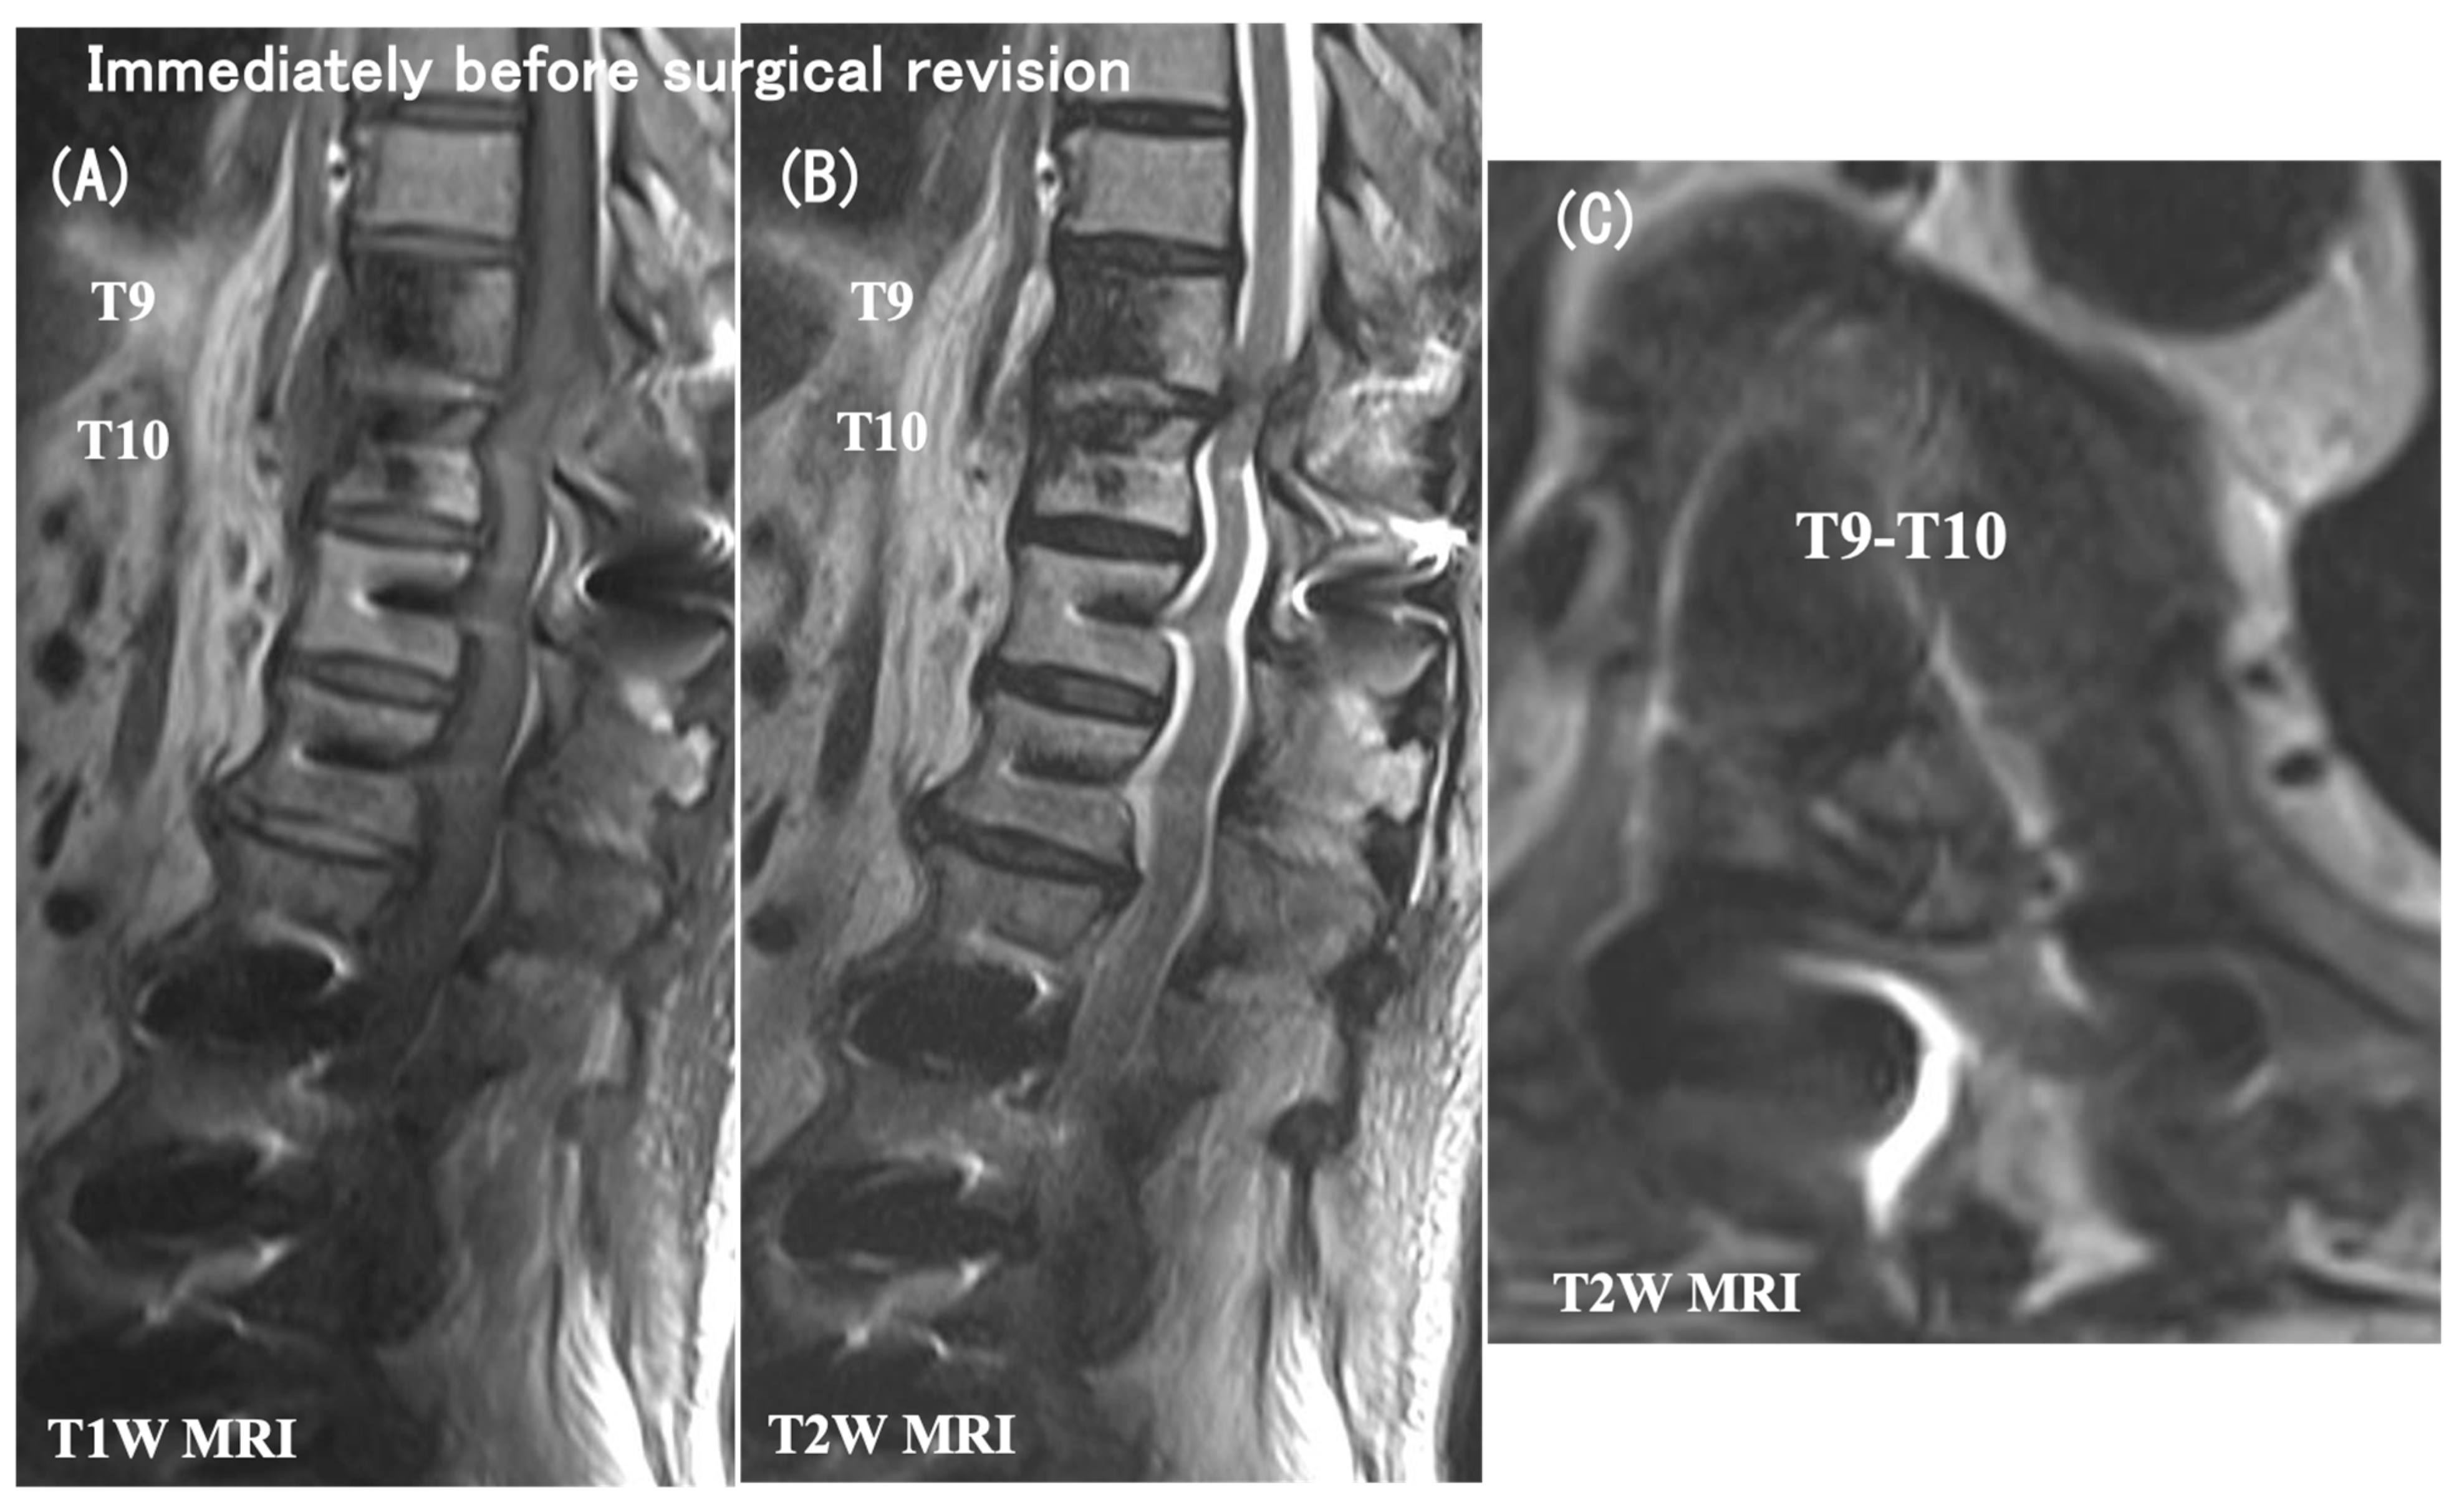

3.6. Case Presentation

- Case no. 6

- 2.

- Case no. 4

| Case No. | Modified Frankel Grade § | Vertebral Collapse | Segmental Instability | Time Interval Between the Initial Op and PJF (month) | Proximal Extension of Fusion | Decompression | Modified Frankel Grade | FU (months) | |||||||||

| 1 | D3 | T8, T10 | – | 13 | T5 | − | D3 | 79 | |||||||||

| 2 | D1 | T10 | UIV–UIV + 1 | 20 | T5 | - | D3 | 37 | |||||||||

| 3 | C | T9, T10 | UIV–UIV + 1 | 4 | T3 | + | D2 | 77 | |||||||||

| 4 | D1 | T10 | UIV–UIV + 1 | 6 | T5 | + | D2 | 40 | |||||||||

| 5 | C | T9 | UIV–UIV + 1 | 14 | T5 | + | D3 | 74 | |||||||||

| 6 | C | – | UIV–UIV + 1 | 2 | T5 | + | D2 | 96 | |||||||||